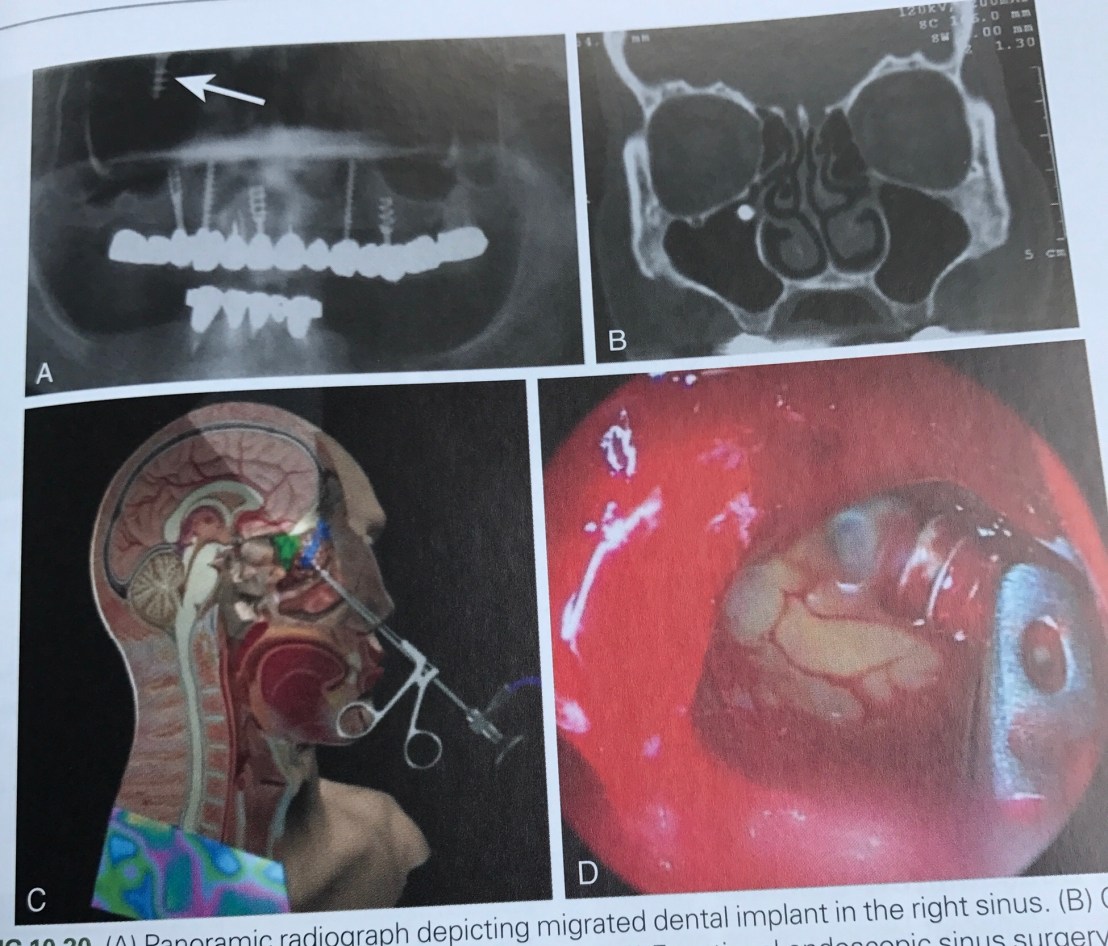

การแก้ไข กรณีเคลื่อนเข้า sinus ครับ ใช้วิธีส่องกล้อง FESS (Fucntional Endoscopic Sinus Surgery)

เคสนี้ Implant เคลื่อนหลุดเข้า Sublingual space ครับ เกิดจาก Lingual plate ที่บางและมี Undercut ทำให้เหมือนวาง Implant ในตำแหน่งที่ Bone คุณภาพแย่มาก

อันนี้โหดหน่อย คือแสดงการเคลื่อนของ Graft จากการทำ Sinus lift ลงไป Submand gland ครับ

กลไกการ migrate คือ ผ่านมาทาง Lymphatic vessels ที่เชื่อต่อจาก Max sinus กับ Submand lymph node

การแก้ไขคือ ต้องควัก Submand gland และ lymph nodes ออก

เคสนี้คือ แสดงการไหลของวัสดุพิมพ์ปาก หรือ วัสดุ Reline เข้า Max sinus ครับ

เป็นข้อควรระวังมากๆ ในกรณีที่ทำหลังจากถอนฟันทันที โดยเฉพาะฟัน 1st molar บน ที่ MB root และ P root ใกล้ Sinus มาก เวลาผสมวัสดุควรใช้ viscosity ที่ไม่ flow มากเกินไป

การแก้ไขในกรณีที่เข้าไปแล้ว คือ refer หมอ Maxillo อย่างเดียวครับ